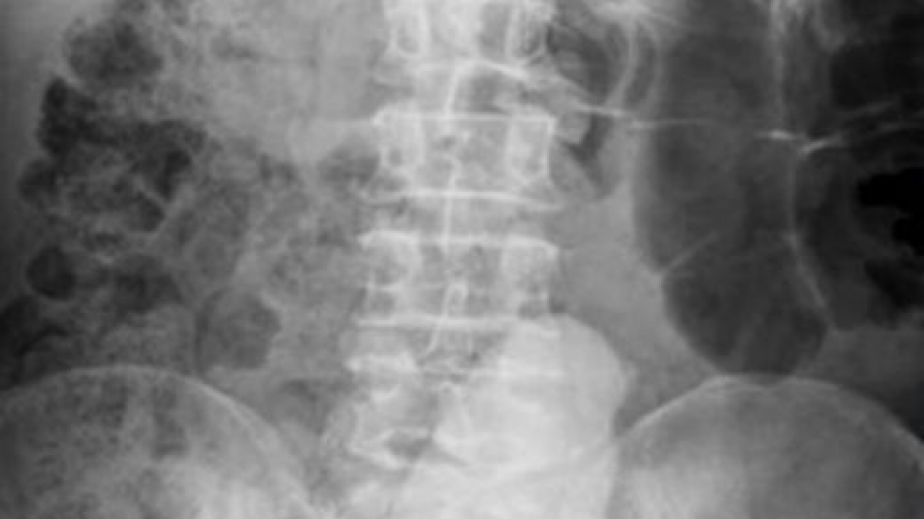

68-годишен мъж отишъл на лекар с болки в кръста и корема,  а лекарите останали с отворени уста, след като направили рентгенова снимка. Странната находка в седалището на 68-годишен мъж се оказал вибратор, дълъг 23 сантиметра. Той бил проникнал много във вътрешността на мъжа и създавал предпоставки за тежкото състояние, пише италианският „Тудей”.Мъжът, който е пенсиониран военен, търпял болките от декември миналата година. Животът му е спасен след оперативна интервенция./БЛИЦ